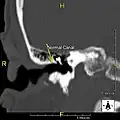

Normal ear canal

Exostosis in ear canal

The normal ear canal is approximately 7 mm in diameter and has a volume of approximately 0.8 ml (approximately one-sixth of a teaspoon).[5] As the condition progresses, the diameter narrows and can even close completely if untreated, although people generally seek help once the passage has constricted to 0.5–2 mm due to the noticeable hearing impairment. While not necessarily harmful in and of itself, constriction of the ear canal from these growths can trap debris, leading to painful and difficult to treat infections.